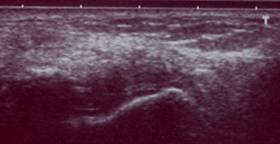

Развитие электронных датчиков на современном этапе увеличило возможности УЗИ. УЗИ ГС в последние годы приобрело особое внимание специалистов. В настоящее время признаётся роль этой технологии в оценке и выявлении целого ряда патологий ГС, и нередко заменяющей МРТ в диагностике повреждений сухожилий и суставов.

УЗИ с применением современных методик позволяет хорошо визуализировать практически все отделы ГС, за исключением губчатого вещества костей, а также внутрисуставные элементы сустава.

В диагностике травматических повреждений комплекса наружных стабилизаторов чувствительность МРТ составила 100%, специфичность 100%. Соответствующие характеристики УЗИ при применении режима тканевой гармоники и трехмерной реконструкции с ультразвуковой ангиографией составили 97% и 88%. Результативность КТ и РГ в этих случаях, по нашим данным, равны нулю. При травматических повреждениях внутренних стабилизаторов информативность МРТ составила: чувствительность 100%, специфичность 88%; УЗИ при применении режима тканевой гармоники и трехмерной реконструкции с ультразвуковой ангиографией составила: чувствительность 97%, специфичность 89%. Чувствительность и специфичность КТ и РГ в той ситуации оказались предельно низкими.